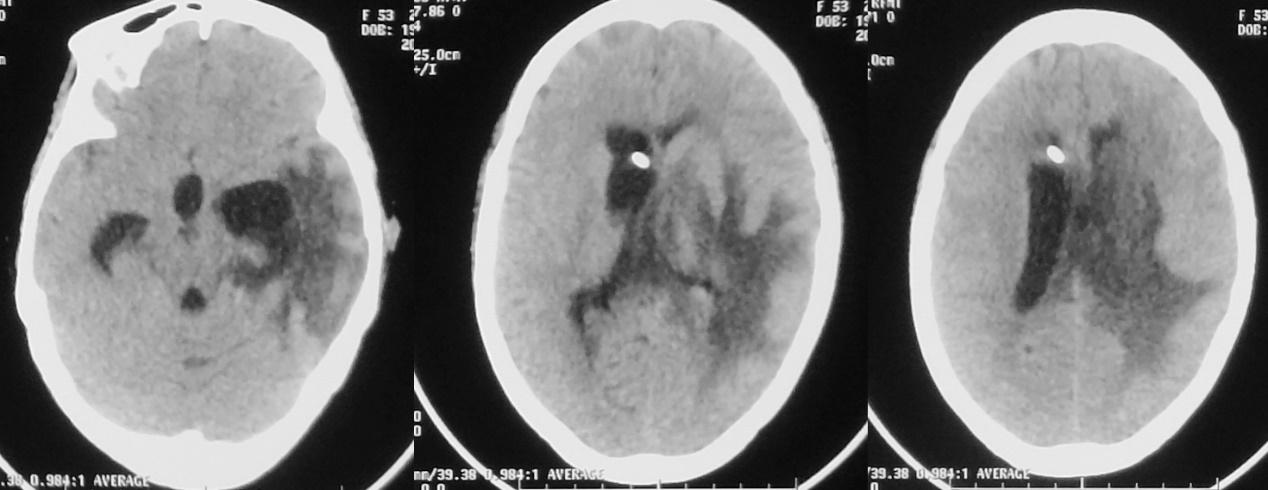

患者体温正常,仍呈朦胧状态,可自动睁眼,刺激肢体可活动。脓肿清除术后第13天,左侧颞角外引流术后第12天,右侧脑室穿刺术后10天,即2020年12月21日,复查头颅核磁( 图-16 )见脑室缩小,丘脑脓肿病灶缩小,左侧脑室枕角和小脑表面的强化灶消失,提示颅内感染好转。

图-16: 2020年12月21日头增强核磁

脑脓肿清除术后第15天,左侧颞角外引流术后第14天,右侧脑室穿刺术后12天,即2020年12月23日,复查头颅CT见术区脑水肿较前(2020年12月16日)减轻( 图-17 )。

图-17: 2020年12月23日头CT

2020年12月24日再次复查头颅CT较前无明显变化( 图-18 )。

图-18: 2020年12月24日头CT

患者意识虽无明显好转,但病情稳定。脑脓肿清除术后第17天,左侧颞角外引流术后第16天,右侧脑室穿刺术后14天,即2020年12月25日,拔除左侧颞角引流管。拔除左侧颞角引流管后3天,复查头颅CT见术区水肿明显,左侧脑室颞角稍扩张( 图-19 )。

图-19: 2020年12月28日头CT

脑脓肿清除术后第23天,拔除外左侧脑室颞角引流管后第6天,即2020年12月31日,患者再次出现昏迷,复查头颅CT( 图-20 )见左侧脑室颞角扩张,右侧脑室引流管脱出。当天再次行左颞角穿刺引流术,同时调整右侧脑室引流管深度后引流通畅。

图-20: 2020年12月31日头CT

第二次左侧颞角引流术后第1天,即2021年1月1日,患者神志明显好转,清醒,可遵嘱动作,复查头颅CT见各脑室较前均缩小( 图-21 )。

图-21: 2021年1月1日头CT